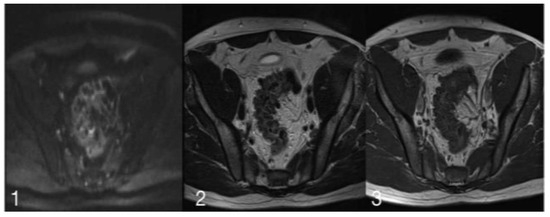

Figure 3.

(1) is a diffusion image with a slice thickness of 6 mm, ET of 74.00 ms and RT of 1900.00 ms. (2) shows a-T2 weighed acquisition, with a slice thickness of 4 mm, ET of 125.00 ms, and RT of 4840.00 ms. (3) is a T1 Turbo Spin Echo image with a slice thickness of 4.5 mm, ET of 12.00 ms and RT of 452.00 ms.

The iconographic MRI evaluation permitted to lay emphasis on the morphological characteristics as well as on the signal. In the presented images, a lack of/low signal in T2 can be observed. The diagnosis of sigmoid diverticulitis may be regarded as one with high probability, but this lack of signal intensity is not found in such a distribution where high signal is present. For this, and for the aforementioned reasons, a high suspicion for a neoplastic lesion in an inflammatory context was stipulated.